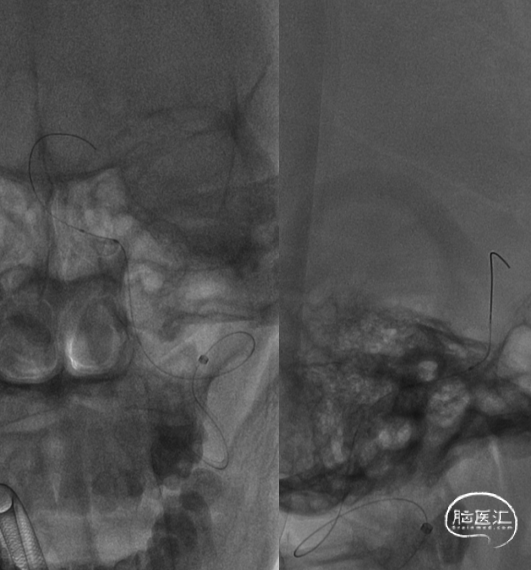

DSA(2022-01-19):

L-ICA

L-VA

R-ICA

复查DSA:左侧椎动脉V4段重度狭窄。

术前影像。

考虑到血管严重扭曲,以长鞘和6FNavien建立路径,微导丝、微导管通过病变。

微导管造影确认真腔。